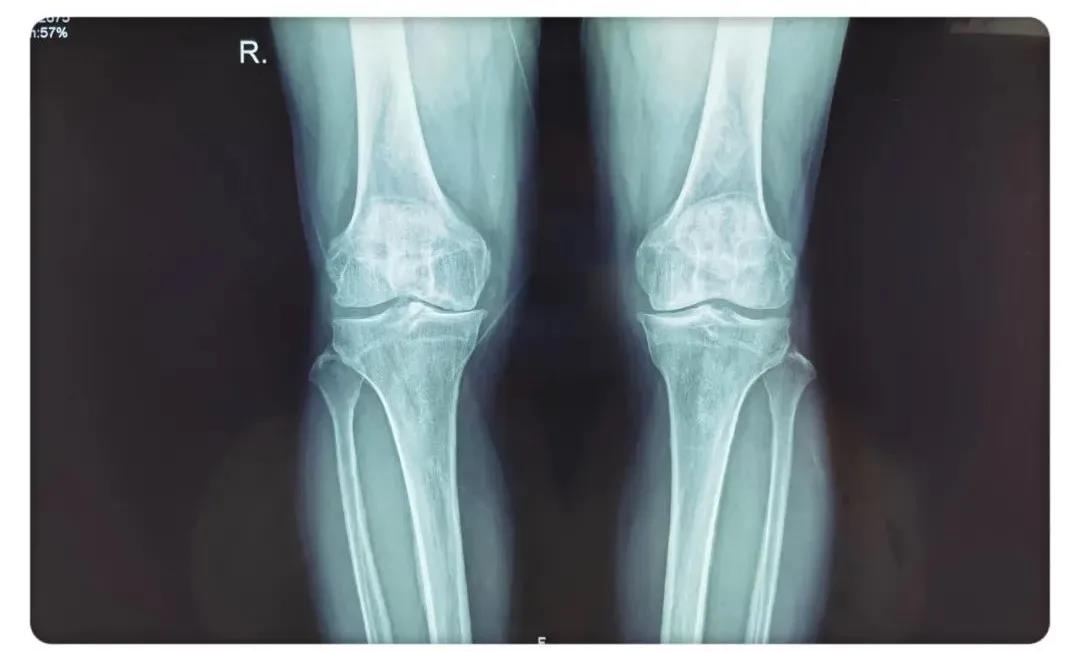

術(shù)前患者腿部X線片